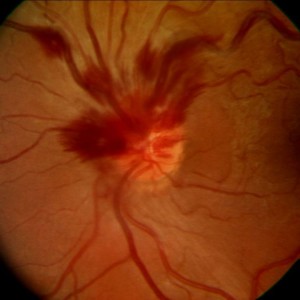

Hemizentralvenenverschluss (اختصارات و إقتصارات: Hemi-ZVV)

| الإنجليزية | hemi-central retinal vein obstruction (اختصارات و إقتصارات: HRVO, HCRVO) |